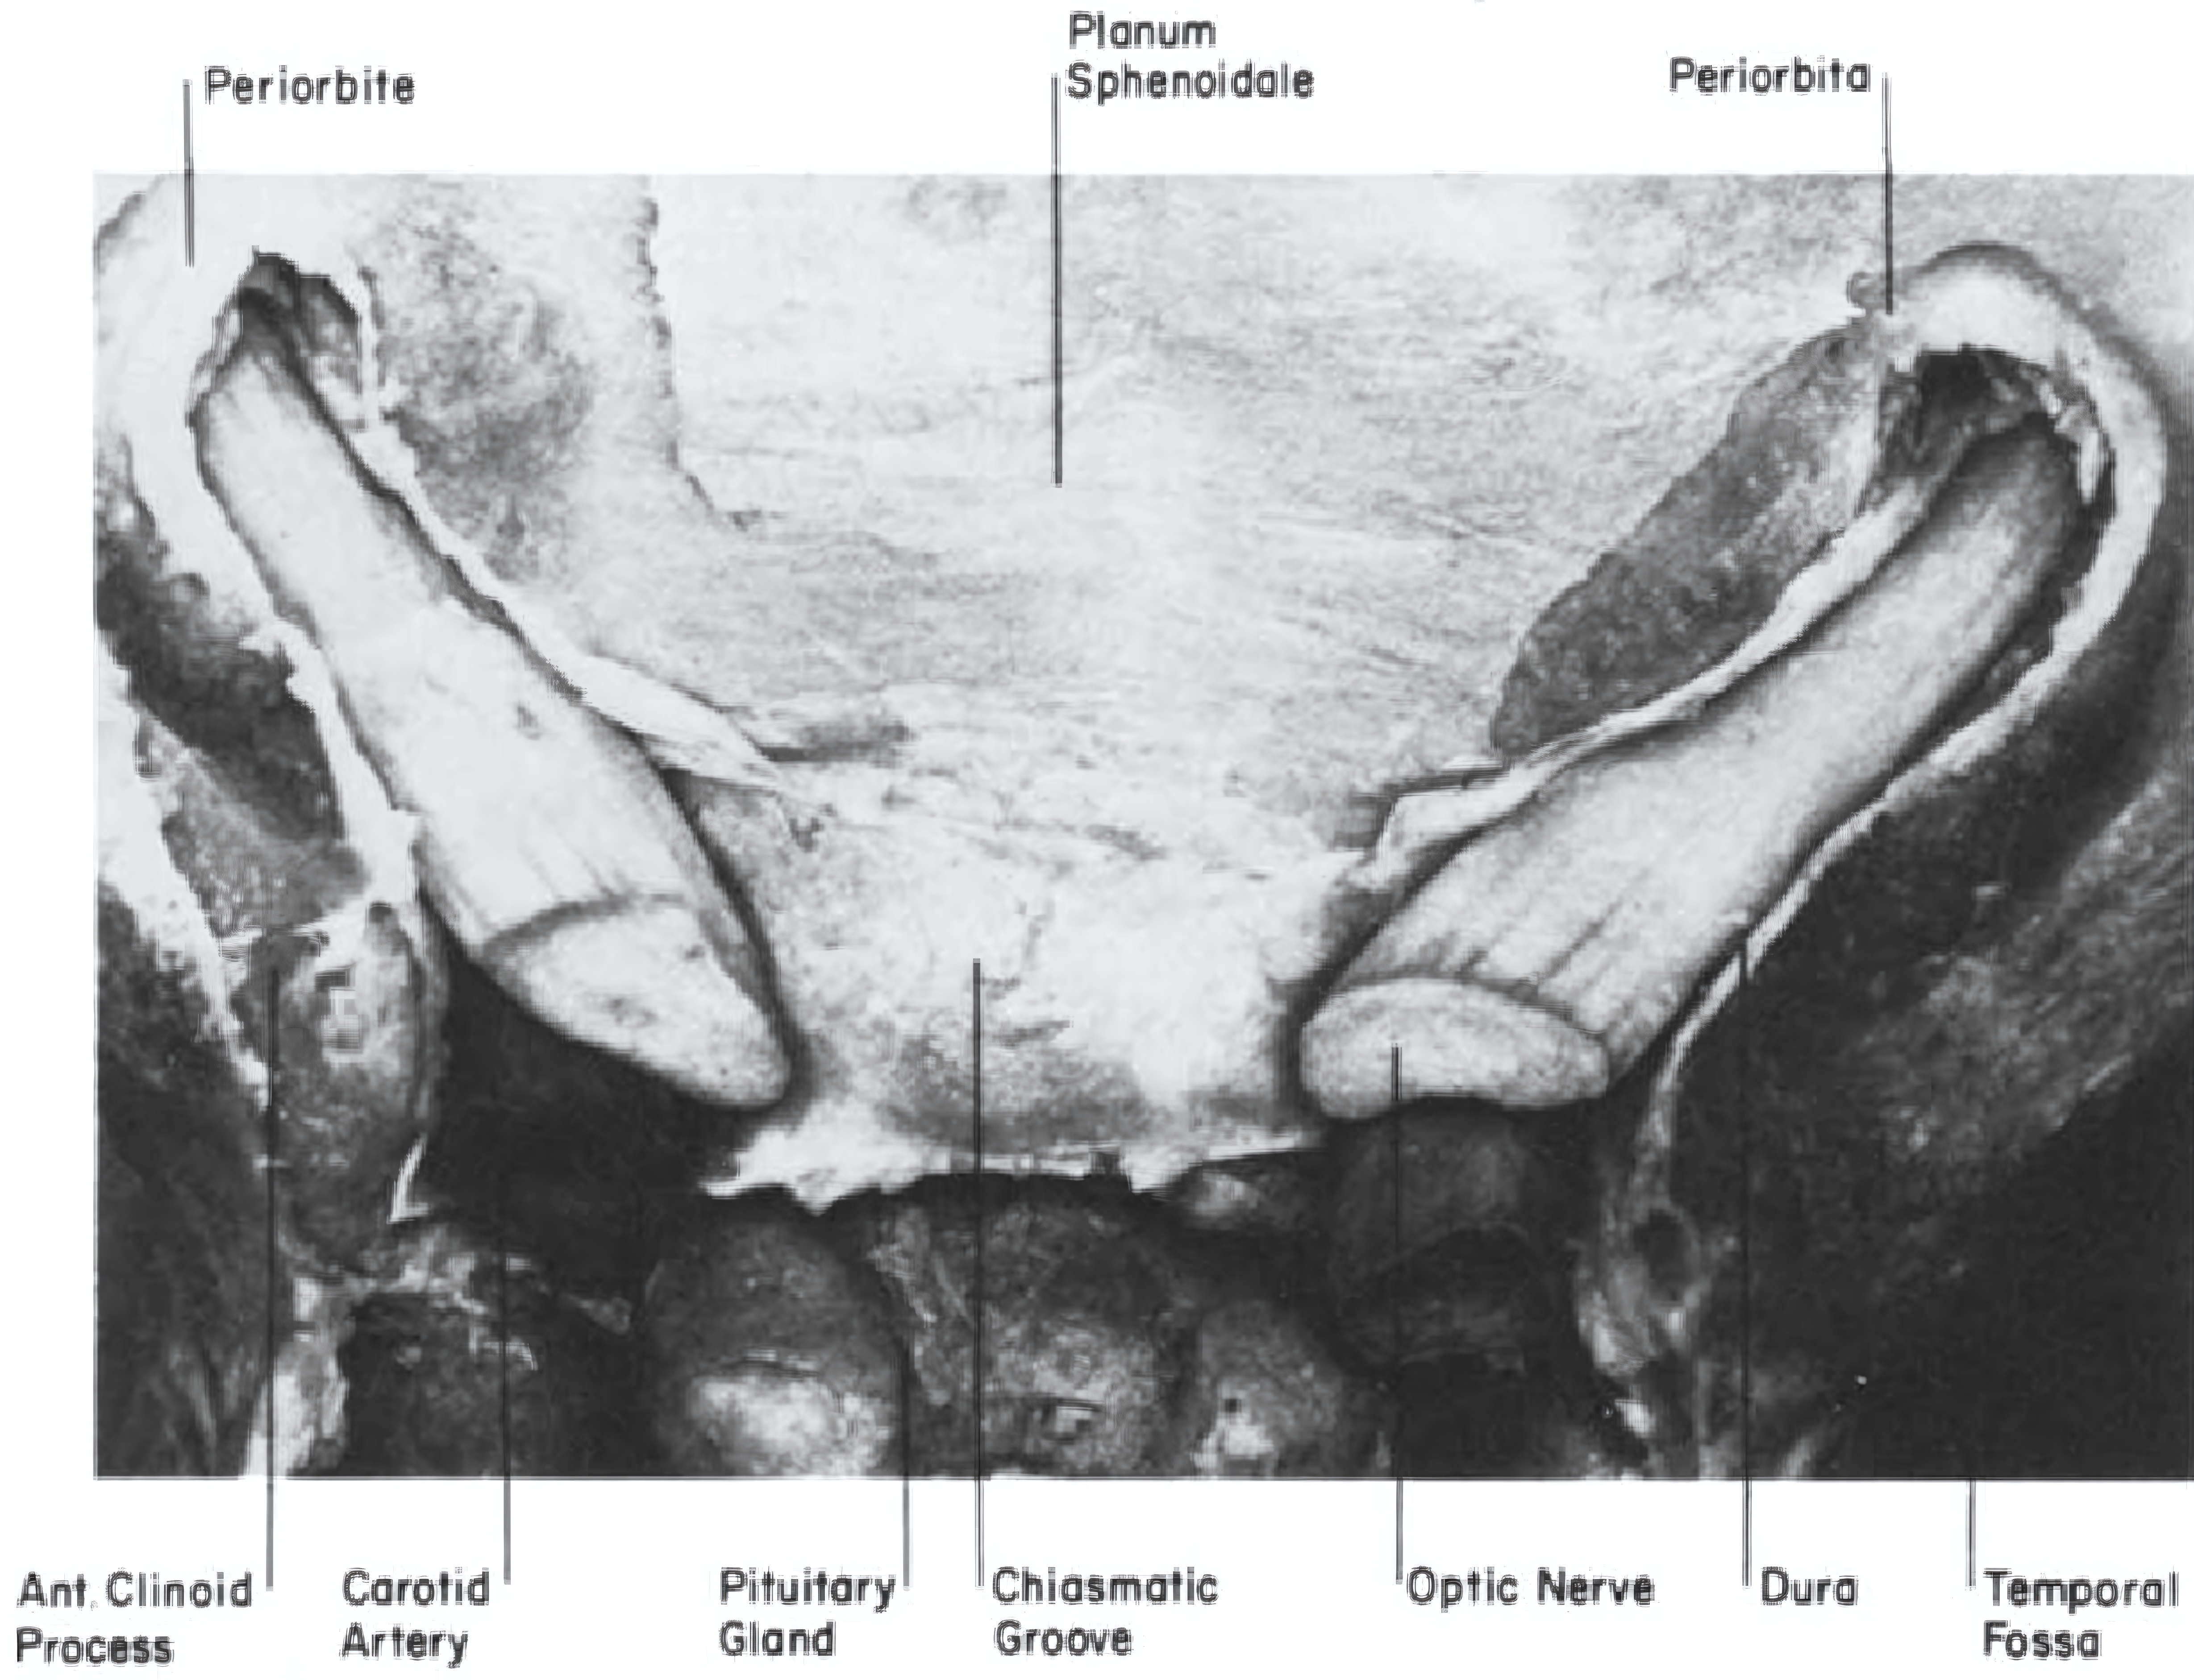

Abbildung

Nervus opticus schematisch

Schematische anatomische Zeichnung des Nervus opticus. Abbildung adaptiert von Habal MB et al. 1977.